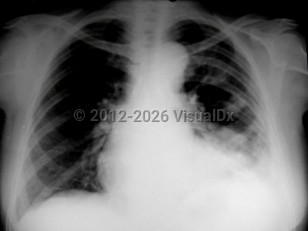

Chest pain, Pleural effusion, 50-59 year old Female

Congestive heart failureCongestive heart failure

Pulmonary edema

Dilated cardiomyopathyDilated cardiomyopathy

Pericardial effusionPericardial effusion